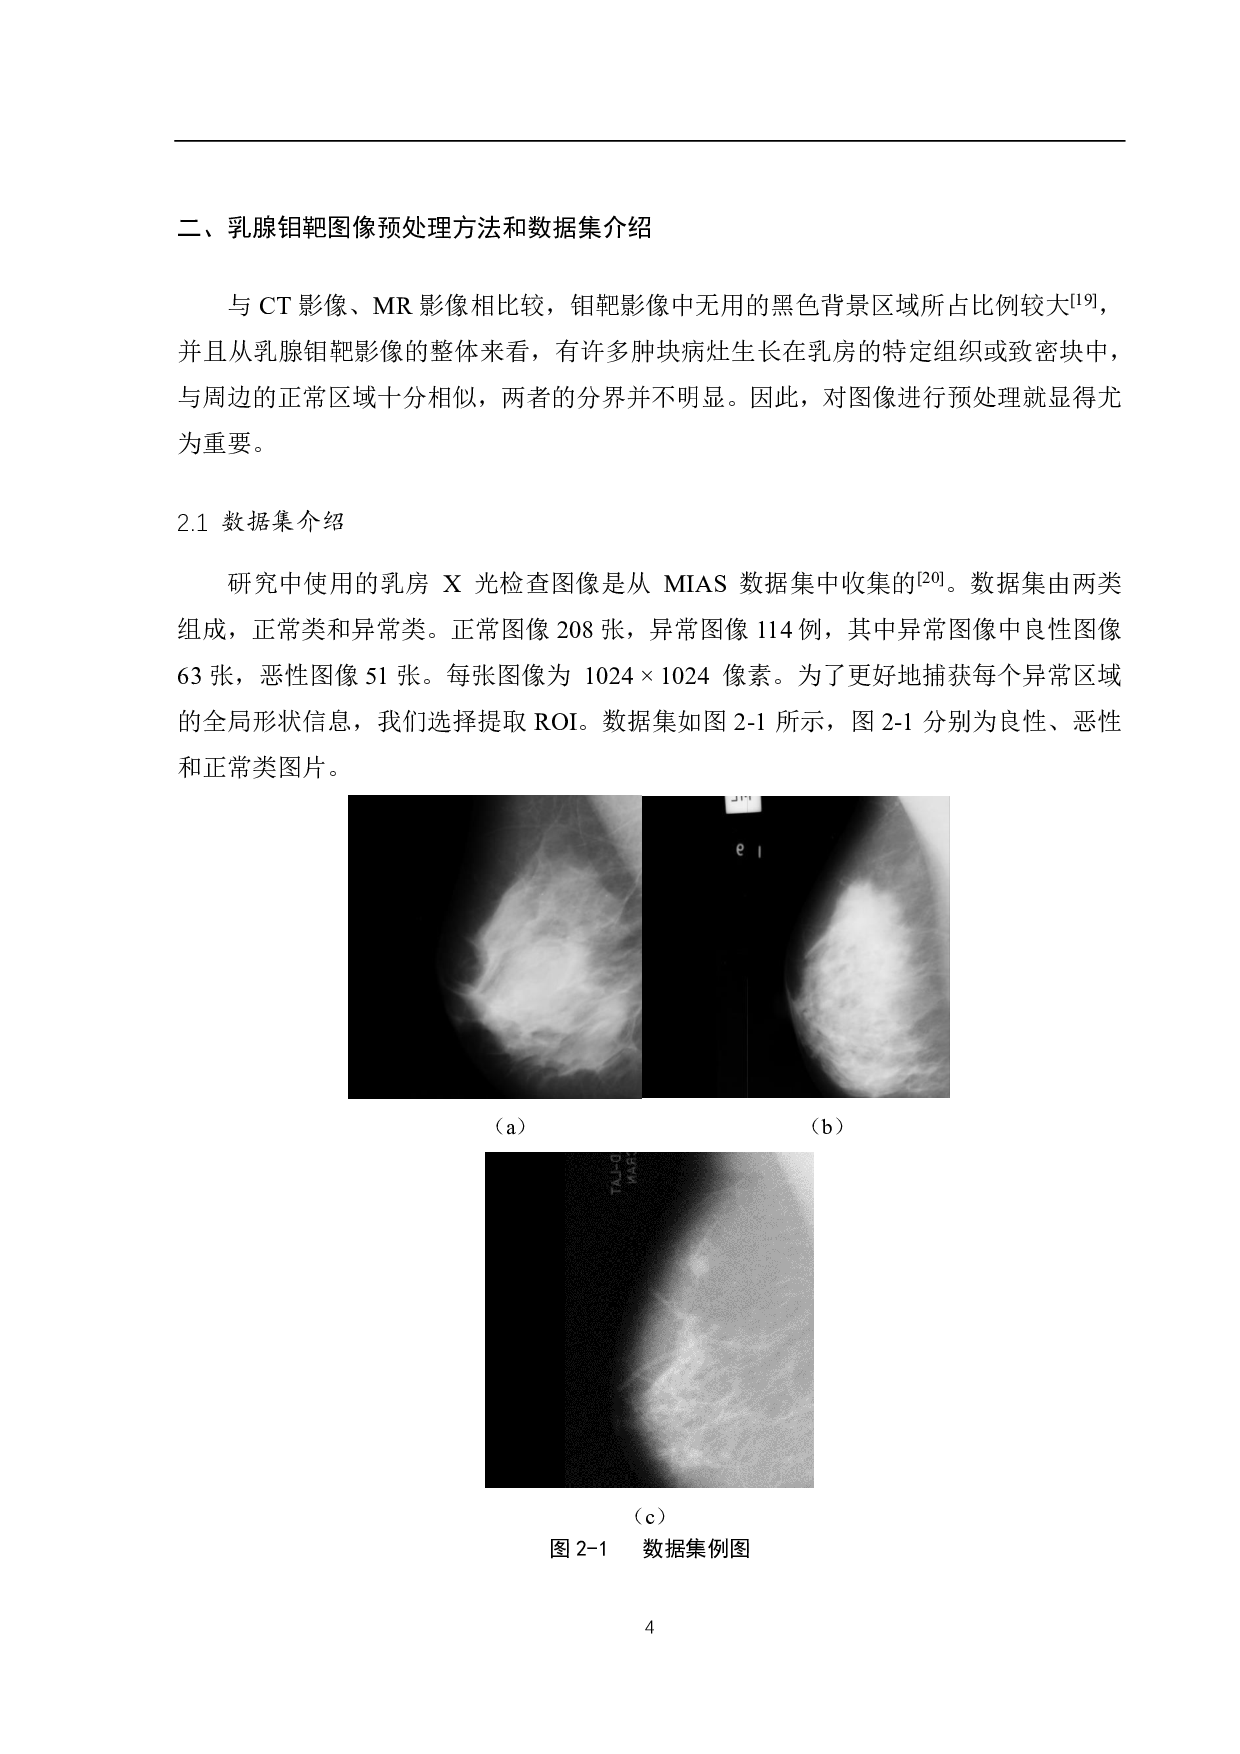

I 基于卷积神经网络的乳腺肿瘤分类算 法研究 作者:常哲 山东中医药大学智能与信息工程学院 2019级生物医学工程专业 指导教师 :王吉阔老师 摘 要 根据世界卫生组织 统计,乳腺癌发病率 高居女性恶性肿瘤的首位, 对人的身心健康 造成了极大危害 。乳腺癌患者病情 复杂并且 临床症状 表现多样 性,因此增加了医生诊断 的难度。为了 降低女性 乳腺癌的死亡率, 开展乳腺肿瘤良恶性分 类模型研究具有非常重 要的理论意义与应用价值 。 本文研究了基于卷积神经网络的乳腺肿瘤 X线钼靶图像良恶性分类 ,使用MIAS数 据集对比 VGG16